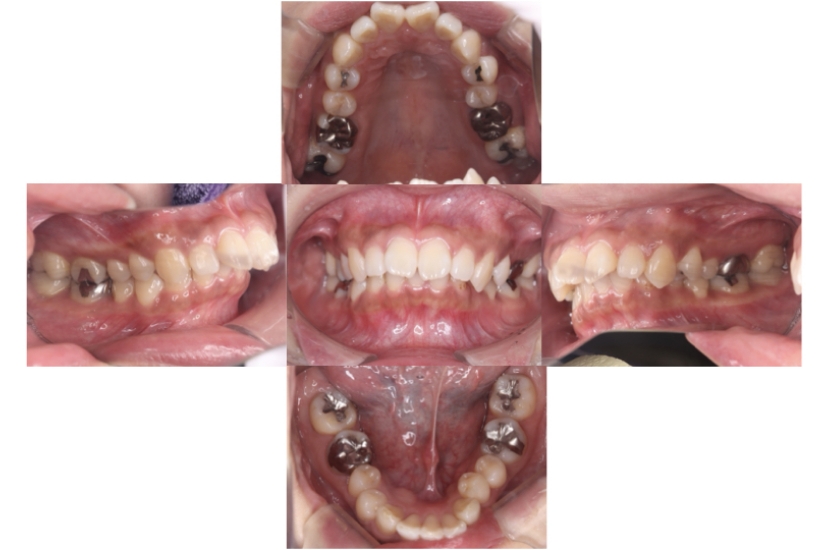

BEFORE

症例1

上顎前突、叢生

抜歯

ブラケット矯正

症例解説

上下顎叢生、上顎前突(出っ歯、上下の前歯のガタガタ)のケースです。

装置はラビアル(上下表側)で、上顎の小臼歯を2本抜歯を行っています。抜歯したスペースを使って、上の前歯の後方移動と叢生(ガタガタ)と出っ歯の改善を行っています。下は歯と歯の間にIPR(隣接面削合)を行い、スペースを確保し、叢生の改善を行っています。

主訴 前歯のガタガタと出っ歯が気になる。

年齢・性別 47歳 女性

お住まいの地域 神奈川県川崎市

治療方針 抜歯スペースおよびIPRを利用して上前歯の叢生(ガタガタ)の改善

抜歯部位 上顎左右第一小臼歯

使用装置 ラビアル(上下表側)、顎間ゴム

治療期間 2年0か月

治療回数 15回

リテーナー クリアリテーナー